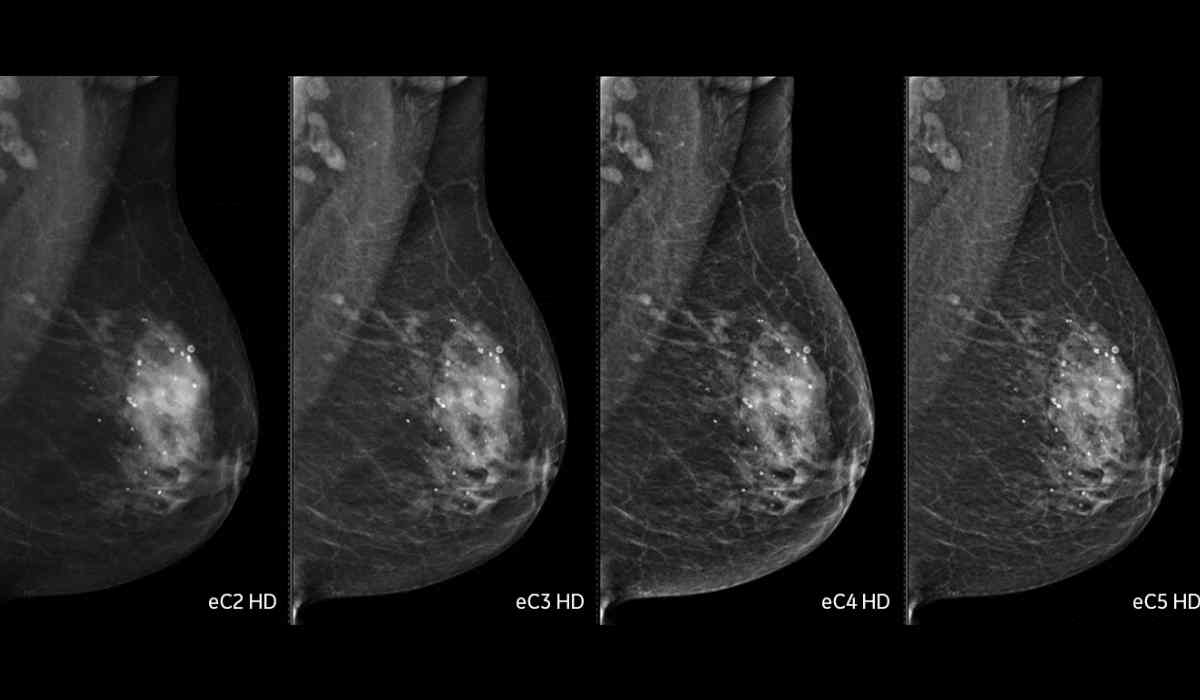

ماموگرافی دیجیتال، جانشین روش معمولی است و نتایج آن روی صفحه نمایشگر به عکس درمیآید. ابزار دیجیتال امکان برسی نتایج در لحظه و اشتراکگذاری آنها بین متخصص رادیولوژی و متخصص زنان را فراهم میکند. توضیحات زیر پشتیبانی میکنند تا با انواع نتایج ماموگرافی، آشنا شوید:

ماموگرافی ۲ بعدی

ماموگرام دیجیتال، زیاد تر شامل حداقل دو عکس از هر پستان در زوایای گوناگون است. طبق معمولً یک عکس از بالا به پایین و فرد دیگر از کنار پستان، گرفته میبشود و نمای دوبعدی دارد. نتیجه مطالعات بسیاری قبول کردهاند که نتیجه ماموگرافی ۲ بعدی، دقت کمتری نسبت به ماموگرافی ۳ بعدی دارد.

ماموگرافی ۳ بعدی

در روش جدیدتر، ماموگرافی سهبعدی، قطعهای بهصورت قوس روی پستان حرکت و تصاویری از بافتهای درونی را ثبت میکند. تصاویر با برنامه کامپیوتری کنار هم قرار میگیرند تا پزشک بافتهای پستان را بهوضوح در سهسپس ببیند. مطالعات نشان دادهاند که ماموگرافی ۳بعدی، تشخیص سرطانها را افزایش میدهد و مقدار مثبت کاذب را پایین میآورد.